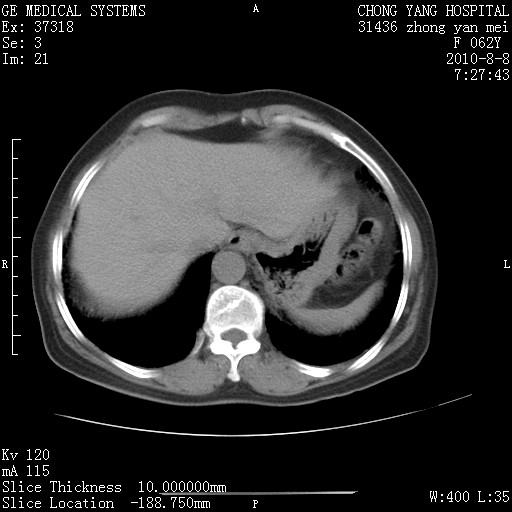

标题: CT28269:F62Y咳嗽胸痛数月。 [打印本页]

标题: CT28269:F62Y咳嗽胸痛数月。

两肺弥漫性间质纤维化伴继发性支扩。

考虑特发性肺间质纤维化

考虑两肺间质性肺炎并肺间质纤维化。

双肺间质纤维化合并感染、肺气肿

双肺间质纤维化

另见右乳腺似有小钙化灶,建议进一步检查。

两肺间质纤维化并牵拉性细支气管扩张。

考虑两肺间质性肺炎并肺间质纤维化,肺气囊形成。

两肺间质改变,纵隔淋巴结肿大,需要考虑结节病的可能。